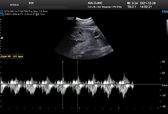

قلب جنین چه زمانی تشکیل میشود؟

قلب در اولین مراحل رشد جنین تشکیل میشود و از اولین اعضای بدن جنین است که رشد و شروع به ضربان میکند و با هر تپشش حس زندگی را در مادر باردار زنده میسازد، ولی آیا میدانید قلب جنین هفته چند بارداری تشکیل میشود؟

هرچند ماهیچه قلب از هفته 4 جنینی شروع به انقباض میکند ولی صدای قلب جنین بوسیله دستگاه سونوگرافی از حدود هفته شش بارداری قابل رویت و شنیدن است.